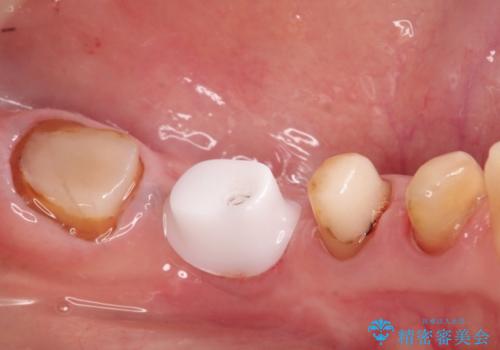

骨の横幅が薄くなっており、インプラントを埋入するには骨幅が足りない状態でした。

まず最初に骨造成を行い、その後にインプラント埋入手術を行うこととなりました。

骨を増やすための手術が必要になるので、通常のインプラント治療より手術回数が一回多くなってしまうのがデメリットですが、将来的に安定したインプラントにするため、骨造成手術を前もって行いました。